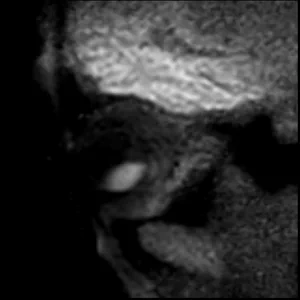

• DWI ADC

DWI ADC

Diffusion weighted imaging provides a valuable biomarker for differential diagnosis.